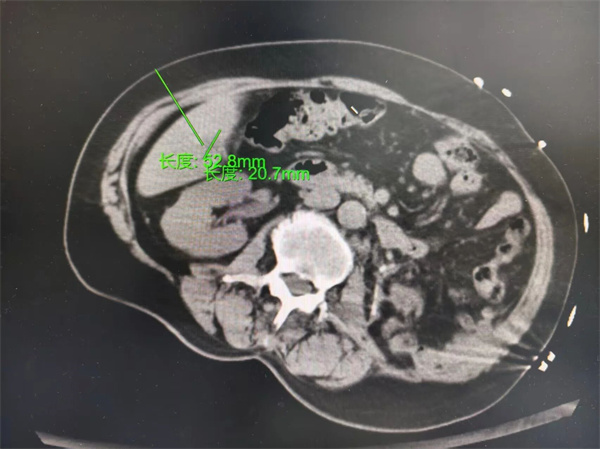

01精准定位

医生会使用超声、CT或增强MRI确定肿瘤位置、大小、血管关系。有时,还需融合影像导航或三维重建技术,像给肝脏装上“GPS”。